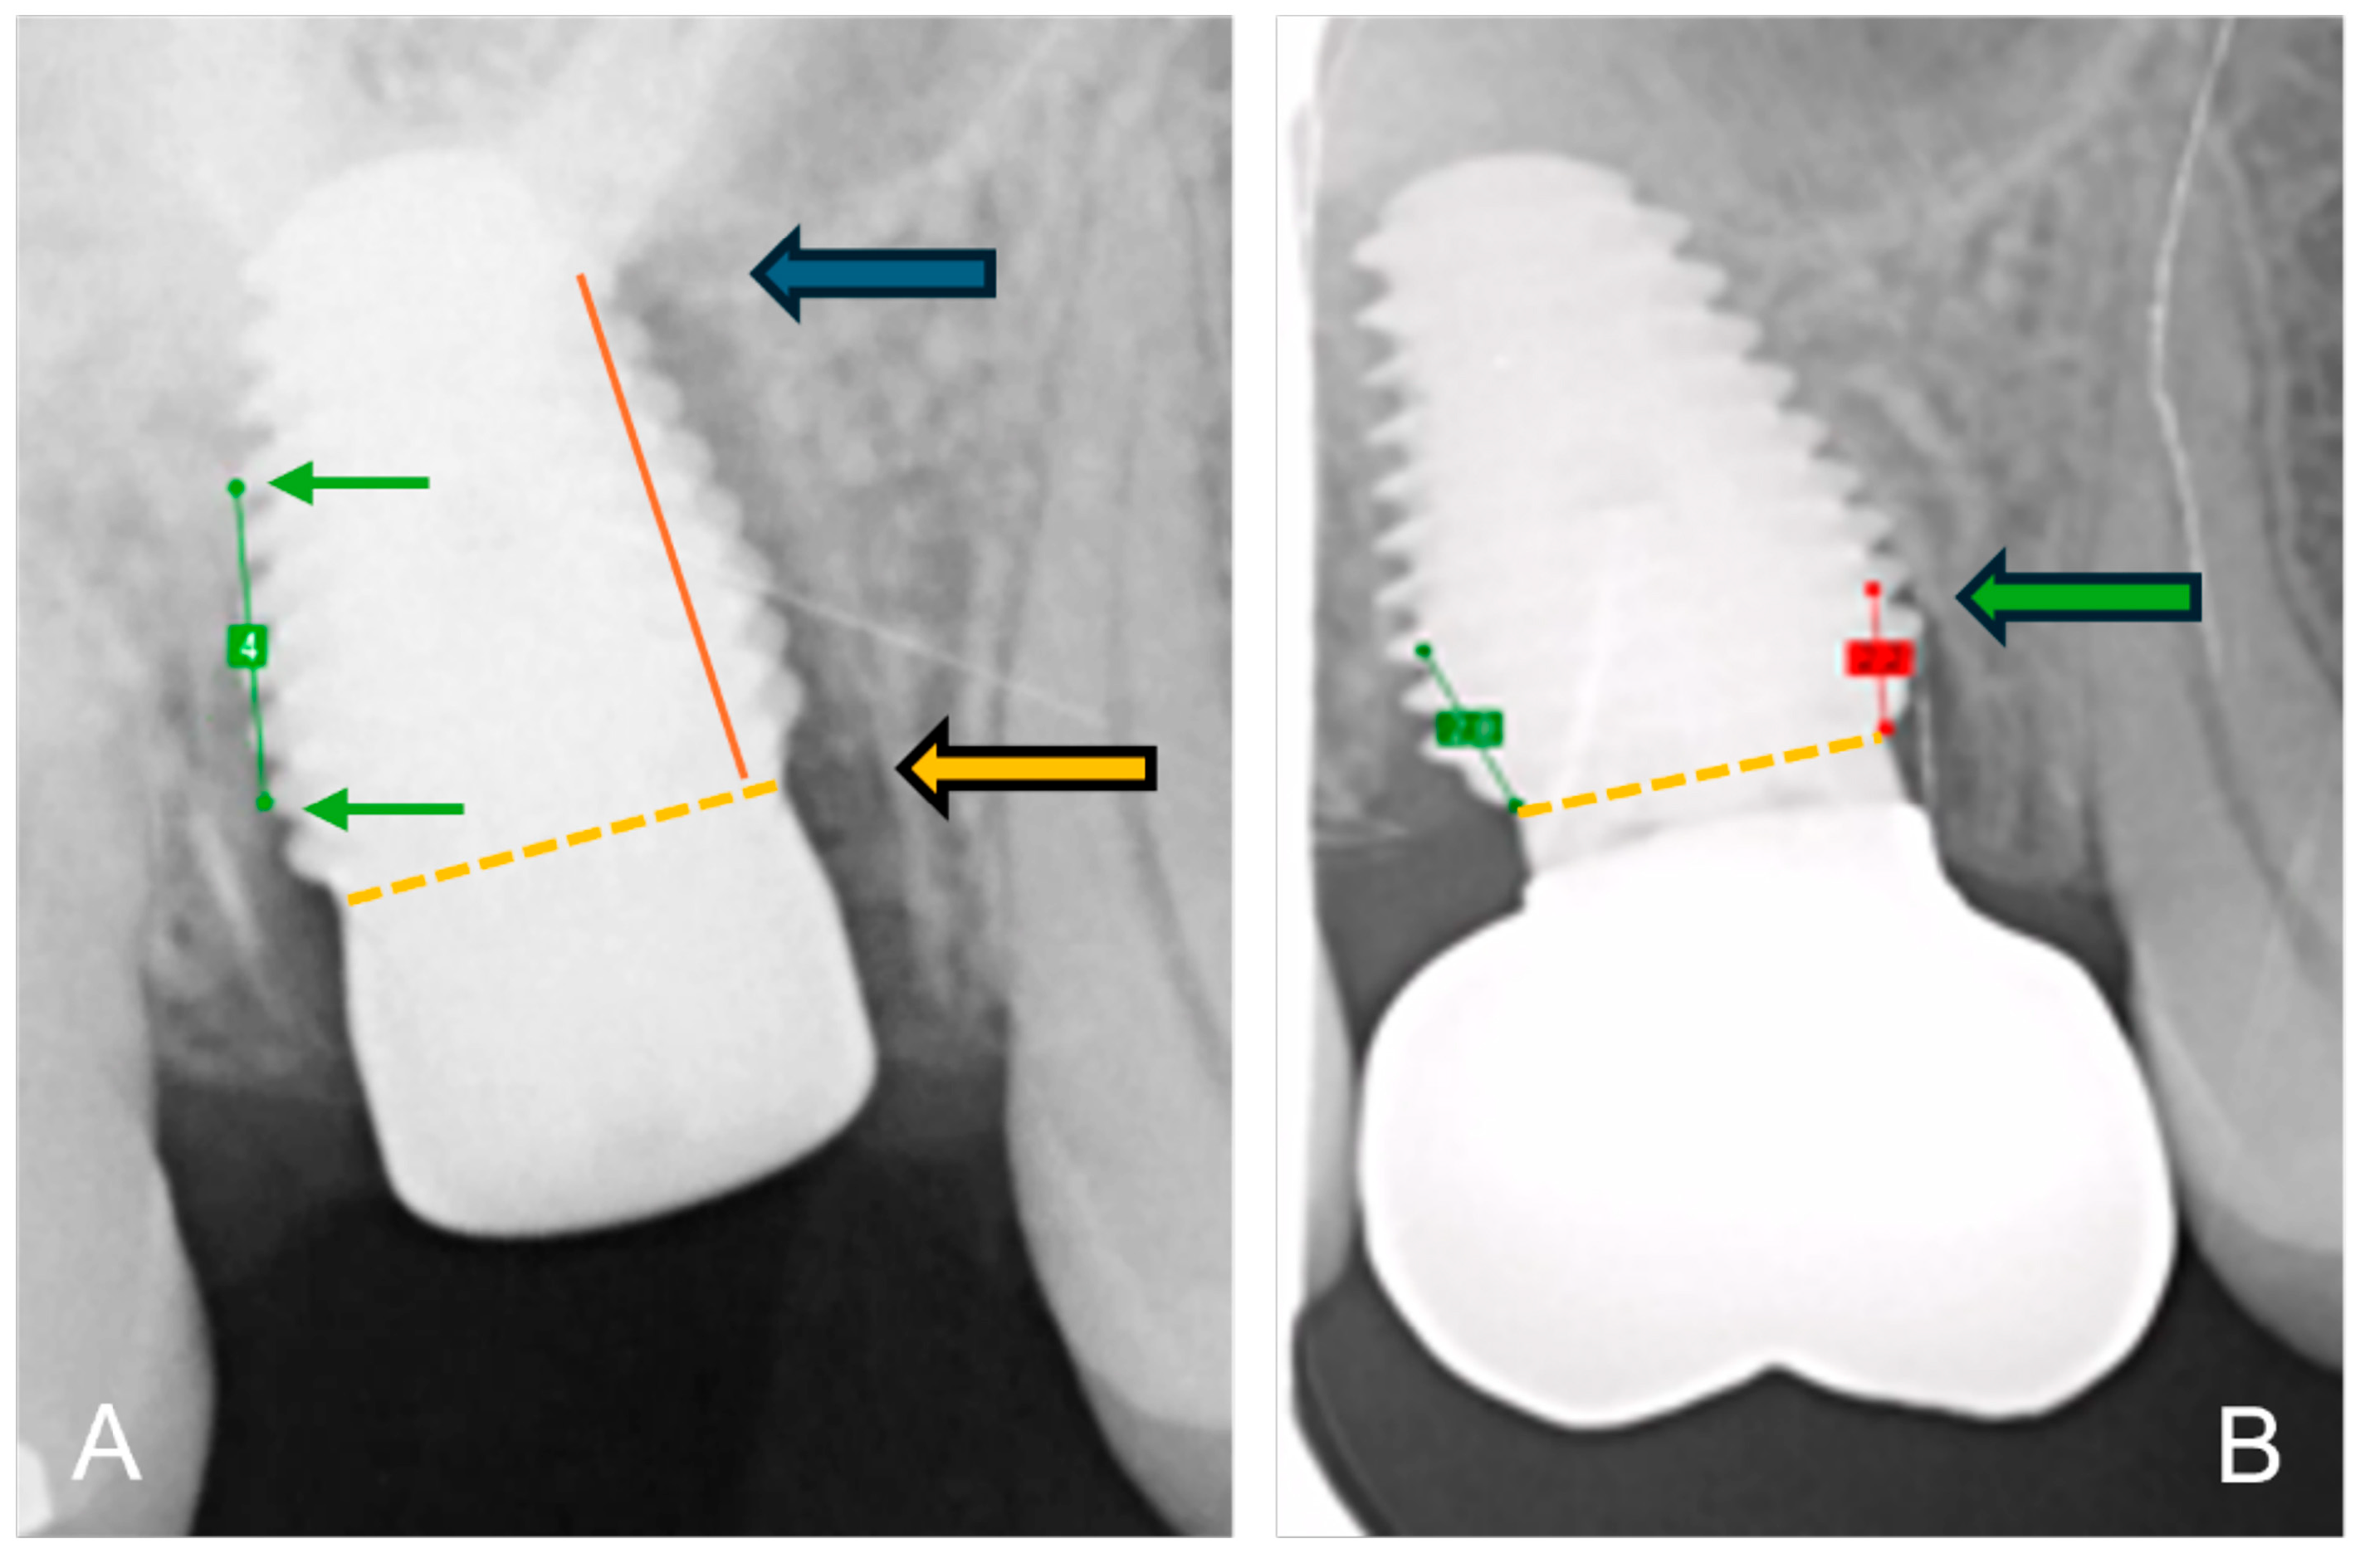

2.5. Radiographic Assessment of Bone Loss

The bone-to-implant contact levels were digitally measured on digital peri-apical radiographs (Software Exquise Classic v.2024, Vertimart, Kwadijk, The Netherlands). According to the workflow applied in the clinic, periapical radiographs were taken after surgery (baseline), after loading, and at the last available recall appointment. In case the implant threads were unclear, related to misalignment of the Röntgen beam, a new radiograph was taken. The distance from the implant-abutment interface to the most coronal bone-to-implant contact was measured both mesially and distally at each of these time points. Measurement errors, due to magnification or angulation of the radiograph, were corrected by calibration with the known distance of 5 implant threads. Three master students, not involved in the actual treatment, measured the radiographs. They were calibrated, and inter-examiner and intra-examiner reliability was assessed by repeating the measurements of 24 implant cases within a 2-week interval. Bone loss at the time of loading and final recall was calculated by subtraction in relation to baseline. Figure 2 demonstrates the method of radiographical assessment of bone levels over time.

Figure 2. Method of radiographical assessment of an immediately placed MAX implant in a molar. Extraction socket; (A) after surgery: green line is the calibrated measurement of 5 implant pitch threads corresponding to 4 mm in reality; the orange dotted line indicates the implant-abutment interface and the orange arrow indicates the reference point; the red line the distance from bone level to reference point and the blue arrow indicates bone level at baseline immediately after surgery; (B) at final recall: the green arrow indicates the bone level at final recall; the red line the distance from bone level to reference point.